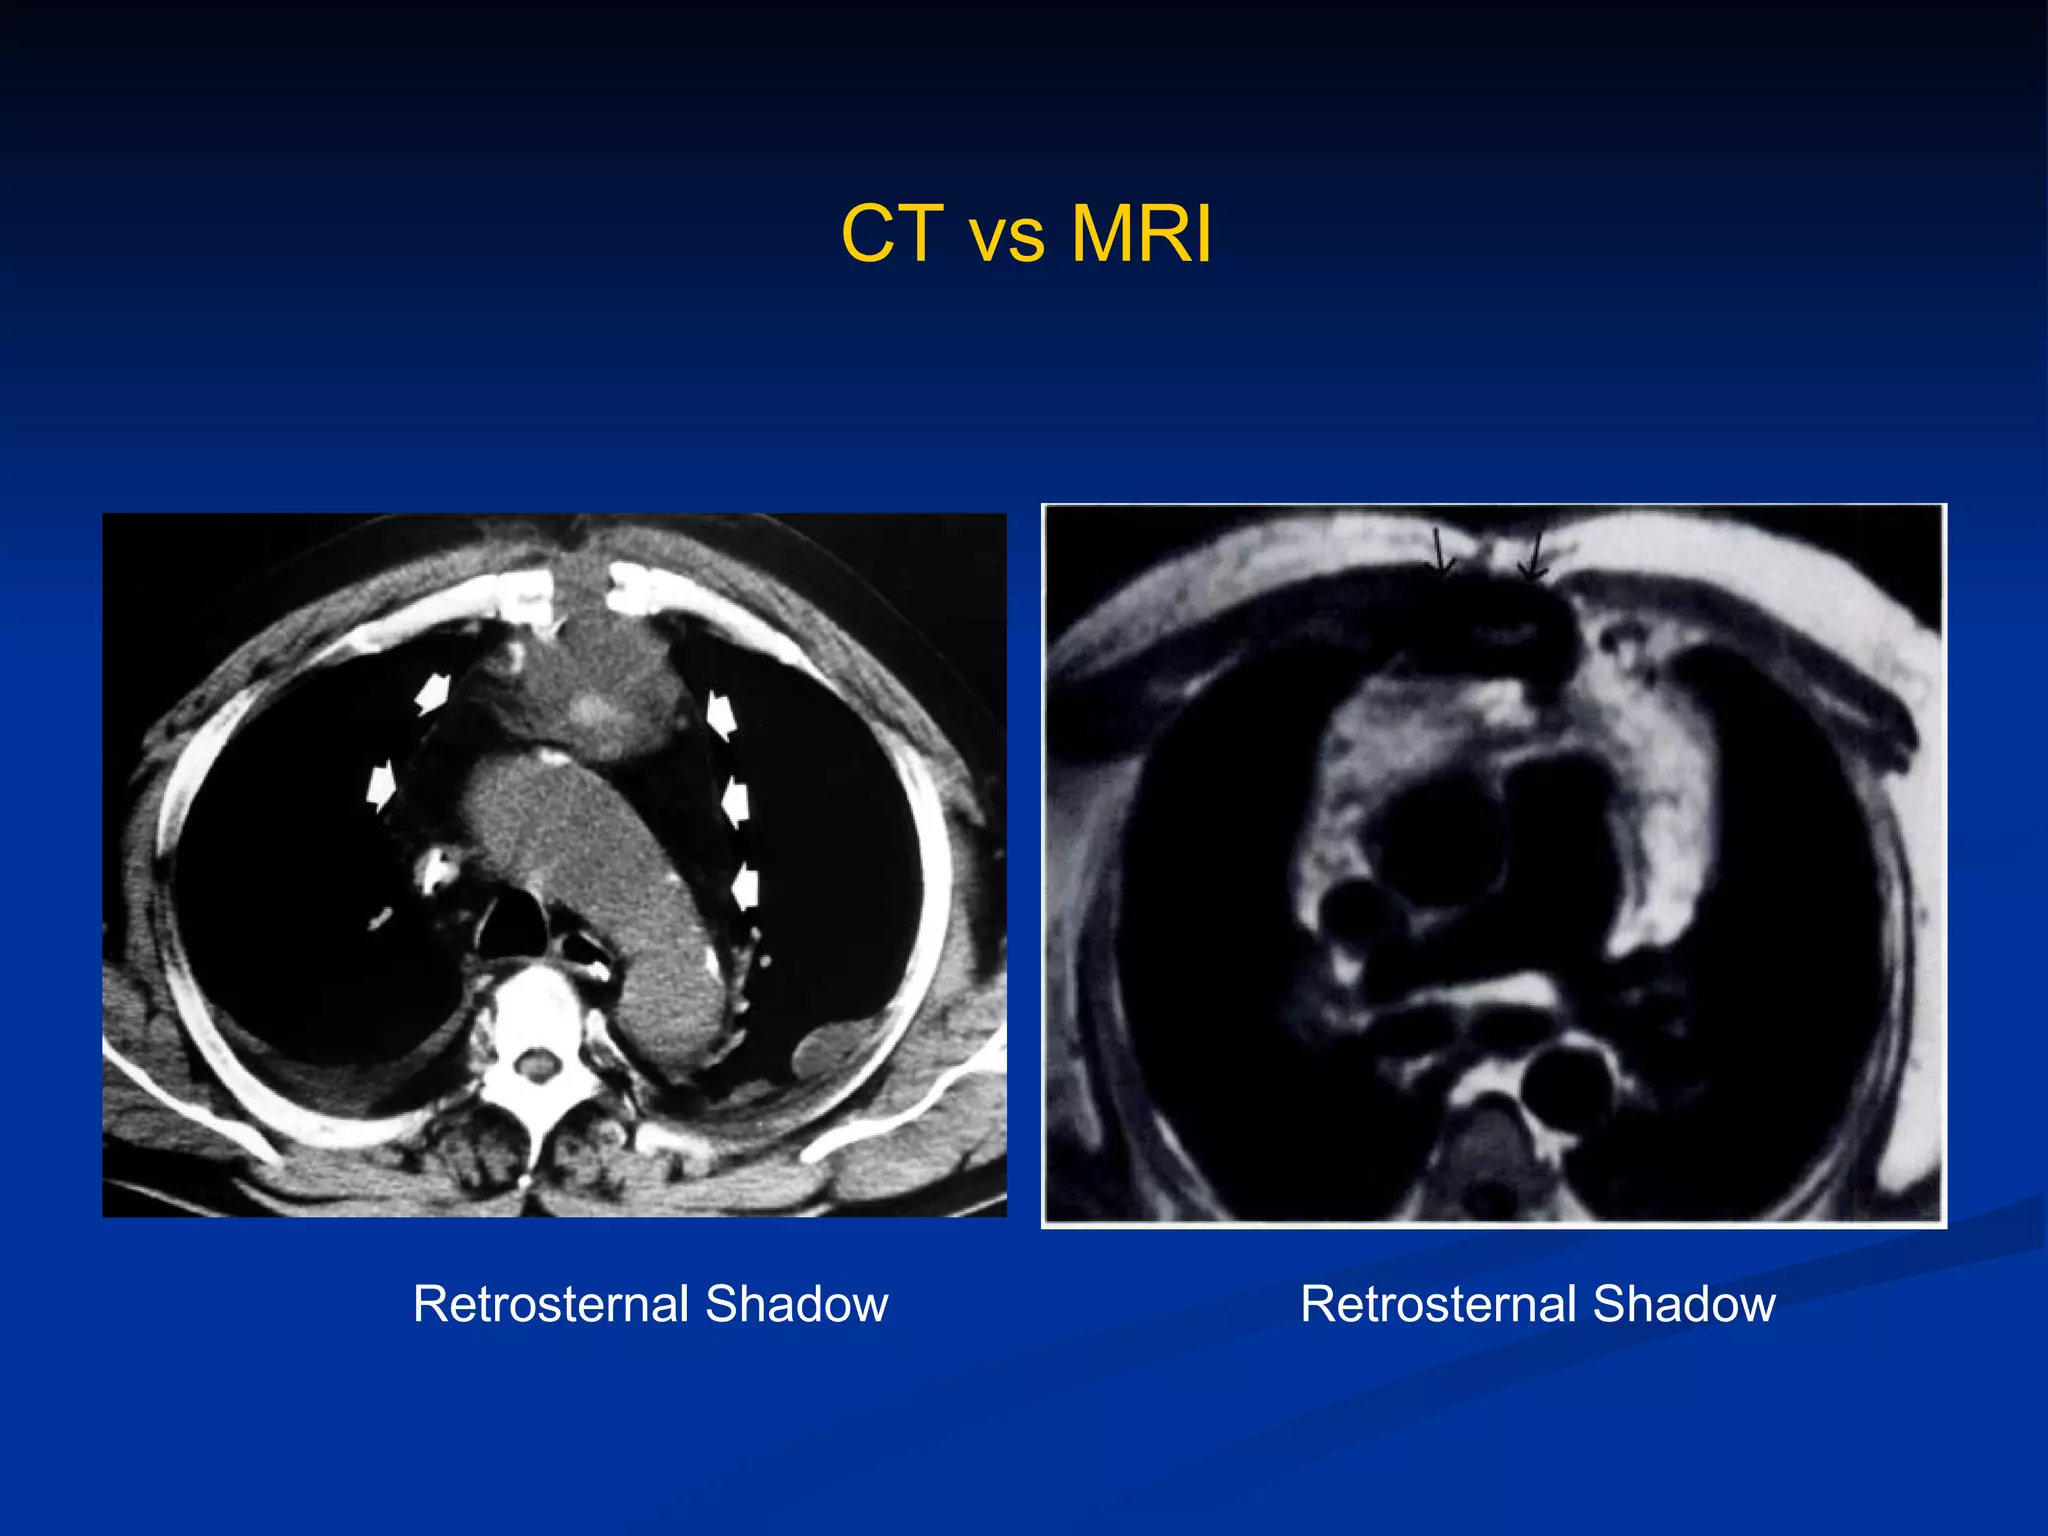

How to make an early diagnosis The  Classic symptoms  and signs of acute infection are  infrequently  encountered   Fever and Leukocytosis  in the absence of local symptoms or signs may be the only presenting clinical features in a small percentage of patients  Wound discharge  is the most common presentation and occurs in 70% to 90%  Local symptoms include wound pain, tenderness, and sternal instability  Chest roentgenograms  are rarely helpful in the early diagnosis  Chest computed tomography scanning with mediastinal aspiration

CT vs MRI Retrosternal Shadow Retrosternal Shadow

How to makean early diagnosis The Classic symptoms and signs of acute infection are infrequently encountered Fever and Leukocytosis in the absence of local symptoms or signs may be the only presenting clinical features in a small percentage of patients Wound discharge is the most common presentation and occurs in 70% to 90% Local symptoms include wound pain, tenderness, and sternal instability Chest roentgenograms are rarely helpful in the early diagnosis Chest computed tomography scanning with mediastinal aspiration

CT vs MRIRetrosternal Shadow Retrosternal Shadow